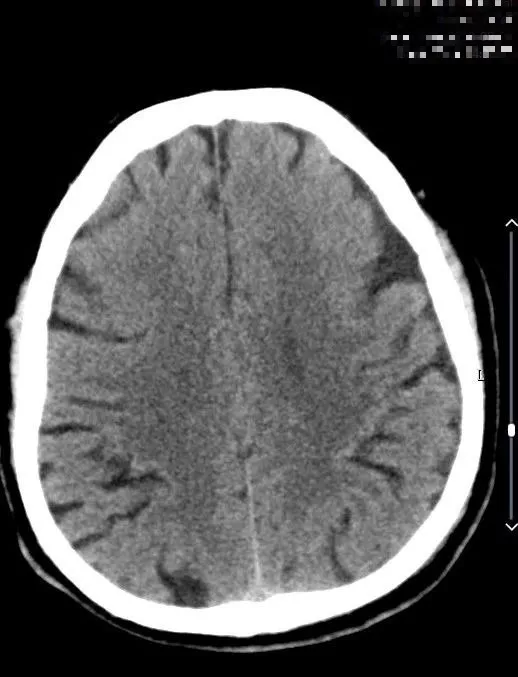

术后24小时内复查头颅CT(08-04日 14:38分)

术后头颈部CTA(08-07日 17:23分)

术后头颅MRI及ASL(08-09日 06:55分)